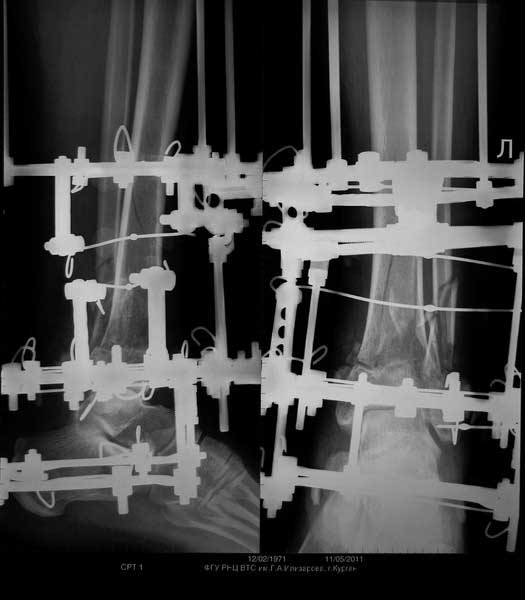

Выставляю случай не менее тяжелый. Фиксация в аппарате Мацукидиса-Шевцова 83 дня, общий срок нетрудоспособности 112 дней. Никаких проблем с остеосинтезом и с последующим лечением не было. Никаких воспалений мягких тканей. 3 перевязки за весь период лечения.Главное - захотеть.